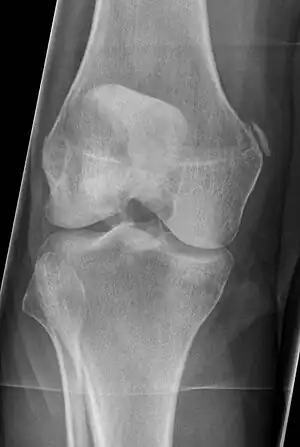

Pellegrini-Stieda syndrome. Also visible is a fracture of the patella.

Pellegrini–Stieda syndrome (also called Stieda disease and Köhler–Pellegrini–Stieda disease) refers to the ossification of the superior part of the medial collateral ligament of the knee. It is a common incidental finding on knee radiographs. It is named for the Italian surgeon A. Pellegrini (b. 1877) and the German surgeon A. Stieda (1869–1945).[1]